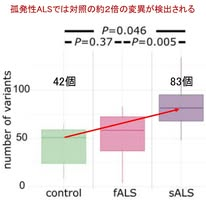

筋萎縮性側索硬化症(ALS)は運動ニューロンが進行性に変性する疾患ですが,その約90%を占める孤発性(非家族性)ALSではその発症機序はよく分かっていません.Brain誌に掲載された研究は,孤発性ALSの原因として「脳の一部の神経細胞にのみ存在する体細胞モザイク変異」が発症に関与している可能性を示した重要な報告です.ドイツのHeidelberg大学を中心とする国際共同研究です.

著者らはまず,剖検脳の運動皮質を試料として,ALS関連遺伝子を標的とした高深度シーケンスと単一細胞RNAシーケンス解析(scRNA-seq)を行いました.高深度シーケンスとは,同じDNA領域を非常に多くの回数読み取ることで,通常の遺伝子解析では検出が難しい低頻度の変異を検出する方法です.本研究では対象としたDNA領域を平均して約2000回(!)読み取る解析が行われ,脳の一部の細胞に存在する可能性のある体細胞モザイク変異を検出できるように設計されています.さらに公開されているscRNA-seqデータを用いて体細胞変異の解析を行い,どの細胞種に変異が多いのかを細胞レベルで検討しました.解析には孤発性ALS 9例,既知の原因遺伝子変異を有する家族性ALS 4例,および対照6例の脳組織を用いました.

まず重要なのが図1です.この図は,各群で検出された体細胞変異の数が示されています.孤発性ALS(sALS)では平均約83個の変異が検出されたのに対し,対照では約42個でした.つまり孤発性ALSの運動皮質ではALS関連遺伝子の体細胞変異が有意に増加していました.一方,家族性ALS(fALS)ではこの増加は認められませんでした.この結果は,孤発性ALSでは生殖細胞系列の遺伝子変異ではなく,脳の中で「新たに生じた体細胞変異」が病態に関与している可能性を示しています.

では,増えていた体細胞変異はどの遺伝子に多いのでしょうか.これを示したのが図2です.直線より上にある遺伝子は,対照と比較してALSのほうで変異が多いことを示します.孤発性ALSでは,MAPT,FUS,NEFH,CCNF,NEK1,TBK1など複数のALS関連遺伝子で変異の増加が認められました.つまり孤発性ALSでも,運動皮質においてALSに関係する遺伝子に体細胞変異が生じている可能性が示されたことになります.

この研究は,運動皮質の一部の神経細胞に体細胞変異が生じ,そこから病態が始まるというモデルを支持する結果といえます.少数の異常細胞から病態が始まり,プリオン様の機序で病理が広がるという現在提唱されているALSの病態モデルとも整合します.この研究には複数のインパクトがあると思います.第一に,「孤発性ALSには基本的に遺伝子変異がない」という従来の理解を見直す必要があるかもしれません.血液検査では検出されない体細胞変異が,脳内の一部の神経細胞で生じている可能性が示されたからです.第二に,ALSが身体の一部から始まり,時間とともに他の部位へ広がっていくという「局所発症」の臨床像を,神経細胞レベルの遺伝子変異という分子機序から説明できるかもしれません.第三に,将来的に体細胞変異を生前に検出できる技術が確立されれば,トフェルセンに代表されるアンチセンス核酸治療などの遺伝子標的治療を,孤発性ALSにも応用できる可能性があります.本研究が示した上記の知見は今後,大きく発展する重要な概念になる可能性があります.